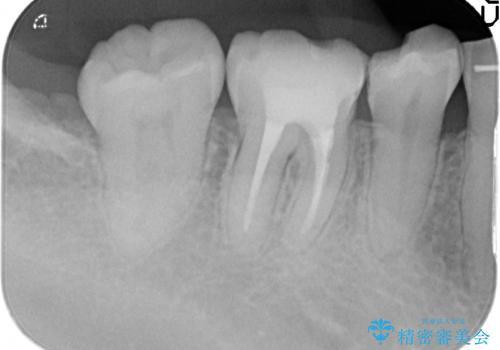

- 治療途中で数ヶ月放置してしまった歯のセラミック治療を希望され来院されました。

セラミッククラウン・セラミックインレーを用いた精密治療を計画します。

審美性、化学的安定性に優れるセラミック治療を行うことができました。